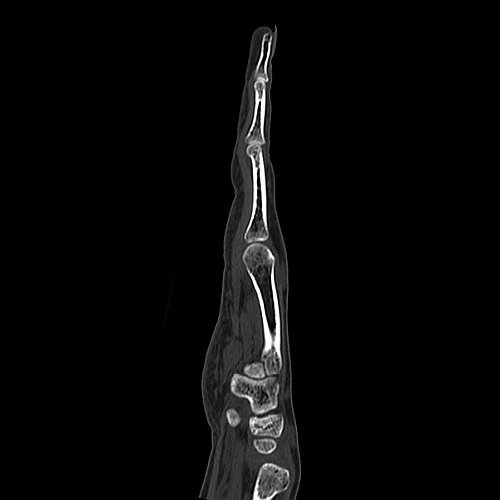

Кисть